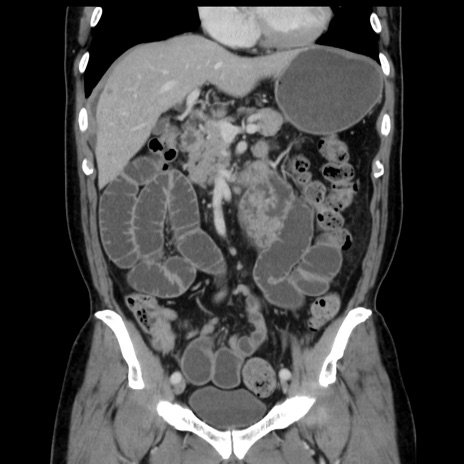

症例16(冠状断像)

【症例】 70歳代男性

【主訴】 腹痛、嘔吐

【現病歴】 約1ヶ月前より間欠的に腹痛と嘔吐あり、当院消化器内科を受診したところCTで多発する肝臓のLDAを指摘され、精査中であった。以降は消化器症状は安定していたが、2日前より嘔気と腹痛があり、同日より排便・排ガスが消失した。改善認めず、 本日、救急外来を受診した。

【既往歴】 大腸ポリープ切除後。

【身体所見】意識清明・会話良好、BT 36.3℃、BP 127/80mmHg、 P 80bpm、腹部:膨満あり、平坦・軟、上腹部正中および下腹部正中に圧痛あり、反跳痛なし、筋性防御なし。

【データ】WBC 7200、CRP 0.77